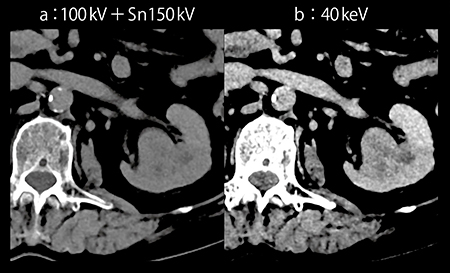

また,腎部分切除術では,腎杯損傷防止のためCT Urography(CTU:排泄相)にて腎杯と腫瘍との距離を確認する必要があるが,排泄相では腎実質の造影の低下により,腫瘍のコントラストが不十分となる。Dual Energy ImagingのMono+は,従来よりもSNRに優れた仮想単色X線画像を作成可能である。120kV相当の画像である100kV+Sn150kV画像では不明瞭な病変も,Mono+の40keV画像ではコントラストが明瞭となる(図2)。

図2 Mono+の40keV画像(c)による腎腫瘍の描出

通常,静脈の評価は皮質髄質相で行うが,静脈腫瘍塞栓は遅いタイミングで評価する必要がある。本症例は体格も大きく,かつ造影剤量も40mLと少ないため,腎実質相での静脈造影効果は不明瞭となってしまう。100kV+Sn150kV画像では静脈の濃染が評価困難であった。しかし,Mono+の40keV画像では造影効果が向上し,腎静脈および下大静脈内の腫瘍塞栓が明瞭に認められた(図3)。静脈のCT値が上昇したことで,十分にウインドウレベルを広げた状態でも病変が観察しやすくなっている。

図3 症例1:Mono+の40keV画像による低造影剤量での静脈描出